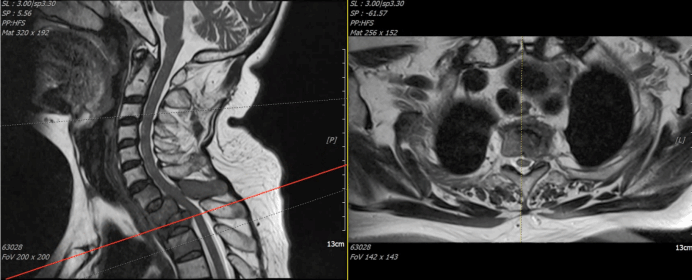

颈胸段脊柱转移瘤是骨病领域治疗难点,其手术术式的选择复杂且棘手。该患者因脊柱肿瘤转移,引发胸1、2椎体病理性骨折,合并脊髓压迫椎管狭窄,进而导致右上肢及胸廓剧烈疼痛,夜间痛剧烈,上肢无力进行性加重。术前评估:病变部位极不稳定,轻微的低能量损伤或任其发展,病变区前柱的不稳定将直接压迫椎体后方脊髓,面临高位截瘫甚至生命危险。骨病与创伤科张纯主任迅速启动全科讨论、胸外科、乳腺中心、麻醉科等多学科会诊,一致决定采取手术干预。

患者术前颈椎MRI